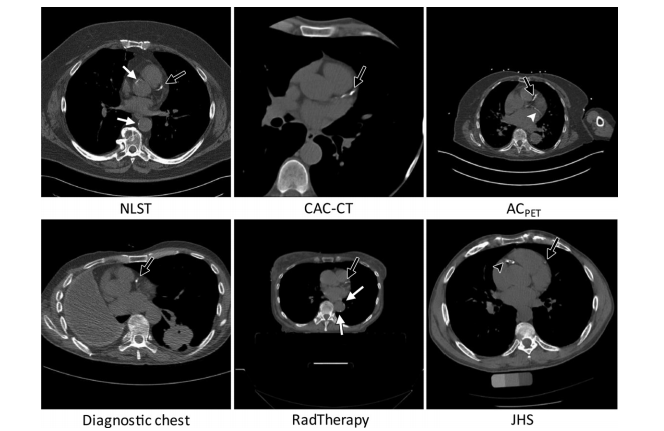

Figure 1: CT images are examples of lung screening CT from the National Lung Screening Trial (NLST), coronary artery calcium scoring CT (CAC-CT), PET attenuation correction (ACPET) CT, diagnostic CT of the chest, radiation therapy treatment planning (RadTherapy) CT, and CT exami nations from the Jackson Heart Study (JHS). Indication of coronary artery calcium in the left anterior descending artery (black arrow), left circumflex artery (white arrowhead), right coronary artery (black arrowhead), and aorta (white arrows).